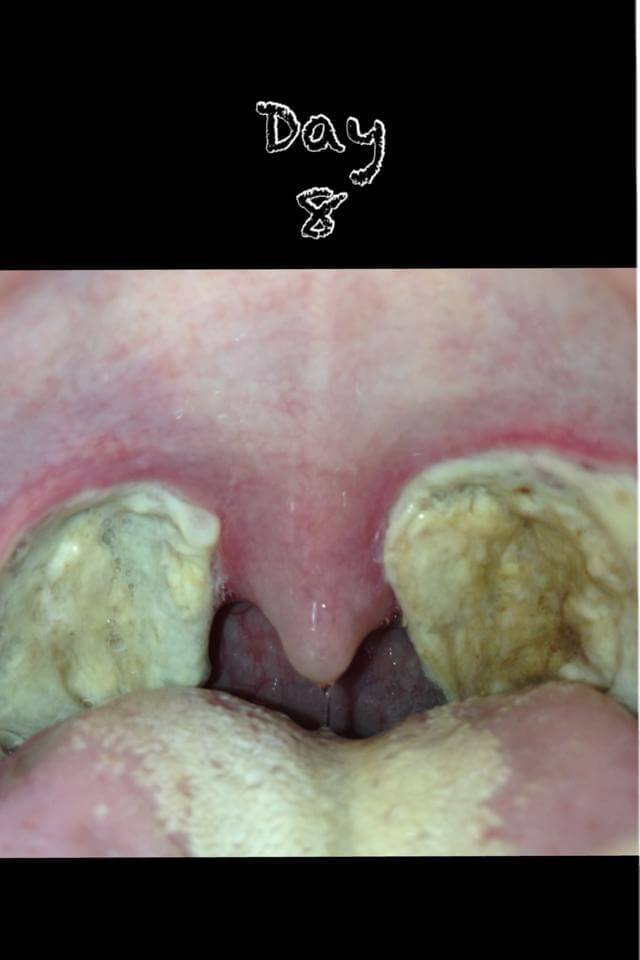

Tonsillectomy Day 8 | Planning and Tonsillectomy Recovery

tonsillectomy scabs pulled out, after tonsillectomy scabs coming off, tonsillectomy recovery scabs falling off, tonsillectomy scabs coming off, tonsillectomy scabs fallen out, tonsillectomy scabs day 4, tonsillectomy scabs and healing